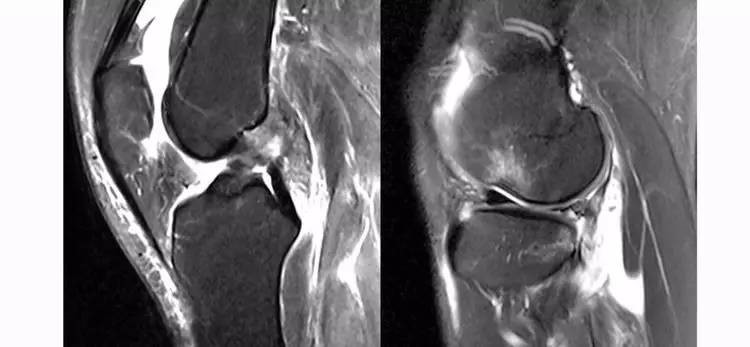

5.假瘤:韧带损伤后断端较整齐,残端组织增生并被滑膜包裹呈'瘤状',如果突出于前方为'独眼征',多见于韧带股骨附着部撕裂及部分撕裂。

12.jpg